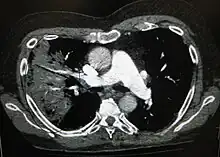

![]() O radiografie alb-negru a pieptului care arată o suprafață triunghiulară albă în partea stângă. Un cerc marchează suprafața. | |

Radiografia toracică este frecvent utilizată în stabilirea unui diagnostic.[14] La persoanele cu forme mai ușoare, radiografia este necesară numai în cazul celor cu posibile complicații, celor care nu răspund la tratament, sau atunci când cauza este incertă.[14][41] Dacă o persoană este atât de bolnavă încât necesită spitalizarea, se recomandă o radiografie toracică.[41] Rezultatele nu indică întotdeauna severitatea bolii și nu deosebesc cu siguranță între infecțiile bacteriene și cele virale.[14]

Radiografiile pot clasifica pneumonia drept pneumonie lobară, bronhopneumonie (cunoscută drept pneumonie lobulară), și pneumonie interstițială.[44] Pneumonia bacteriană, existentă în comunitate, prezintă de regulă consolidarea pulmonară a unui lob pulmonar, fiind cunoscută drept pneumonie lobară.[24] Cu toate acestea, rezultatele pot varia, iar alte caracteristici sunt obișnuite în alte tipuri de pneumonie.[24] Pneumonia de aspirație poate prezenta opacități bilaterale mai ales la baza plămânilor și pe partea dreaptă.[24] Este posibil ca în unele cazuri radiografiile pneumoniei virale să pară normale, să aibă un aspect hiper-inflamat sau să pară similare pneumoniei bacteriene cu consolidare lobară.[24] Este posibil ca în stadiile incipiente ale bolii să nu existe semne depistabile radiologic, mai ales în cazul deshidratării; sau pot fi dificil de interpretat în cazul persoanelor obeze sau care au antecedente de afecțiuni pulmonare.[15] O tomografie computerizată poate oferi informații suplimentare în cazurile incerte.[24]